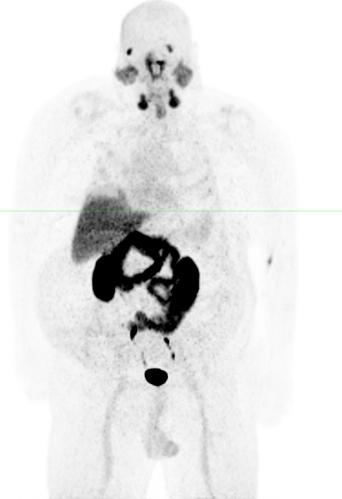

Recent data from over 250 patients treated in investigator sponsored trials with 225Ac-PSMA agents, including both patients previously treated with 177Lu-PSMA radiopharmaceuticals (approximately 100 patients) and 177Lu-PSMA

radiopharmaceutical therapy naïve patients, have shown compelling clinical data and biochemical response rates (including PSA50) and a tolerability profile that we feel supports further development of an alpha-based 225Ac therapeutic candidate.

img67593536_4.jpg

The example above shows gallium-68 PSMA-11 PET/computed tomography scans of one patient who was treated with 177Lu-PSMA-617 and subsequently with 225Ac-PSMA-617 (Figure: Kratochwil, C. et al. 225Ac-PSMA-617 for PSMA-Targeted α-Radiation Therapy of Metastatic Castration-Resistant Prostate Cancer. The Journal of Nuclear Medicine. Vol. 57 No. 12. December 2016). The first image shows the initial tumor spread (A), then restaging after two cycles of 177Lu-PSMA-617 presenting progression (B). In contrast, restaging after two cycles of 225Ac-PSMA-617 is shown in the third image (C) and the final image after an additional cycle of 225Ac-PSMA-617 (D) presented an impressive radiographic response.